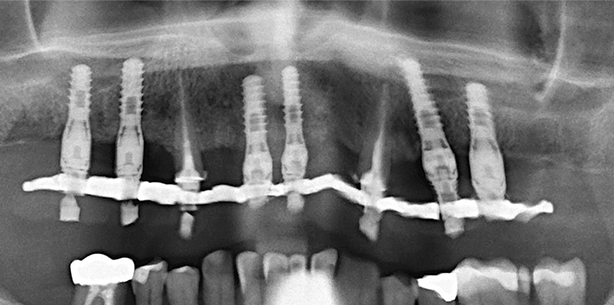

Für das Implantat 42 wurde ein Aufbau mit 15 Grad Abwinkelung gewählt, bei 32, 34 und 36 kamen gerade Aufbauten mit 2 mm bzw. 3 mm Höhe zum Einsatz, bei 45 und 46 gerade Aufbauten mit 1 mm Gingivahöhe. Die Overdenture-Titankappen wurden aufgesetzt und in der Schablone fixiert. Im nächsten Schritt wurde die intermaxilläre Relation mit der Schablone bestimmt. Zwei Tage postoperativ wurde der Zahnersatz spannungsfrei eingeschraubt, die Schraubenkanäle mit Kunststoff verschlossen und der Biss feinjustiert (Abb. 8).

Es stellte sich ein 73-jähriger Patient mit insuffizienter Frontzahnbrücke und extraktionswürdigen Zähnen 34, 33, 32, 42 und 43 (Abb. 12) vor. Auf sechs Implantaten wurde ein definitiver Zahn-ersatz nach dem Protokoll des „Set-on-six“-Systems eingegliedert (Abb. 13 und 14).